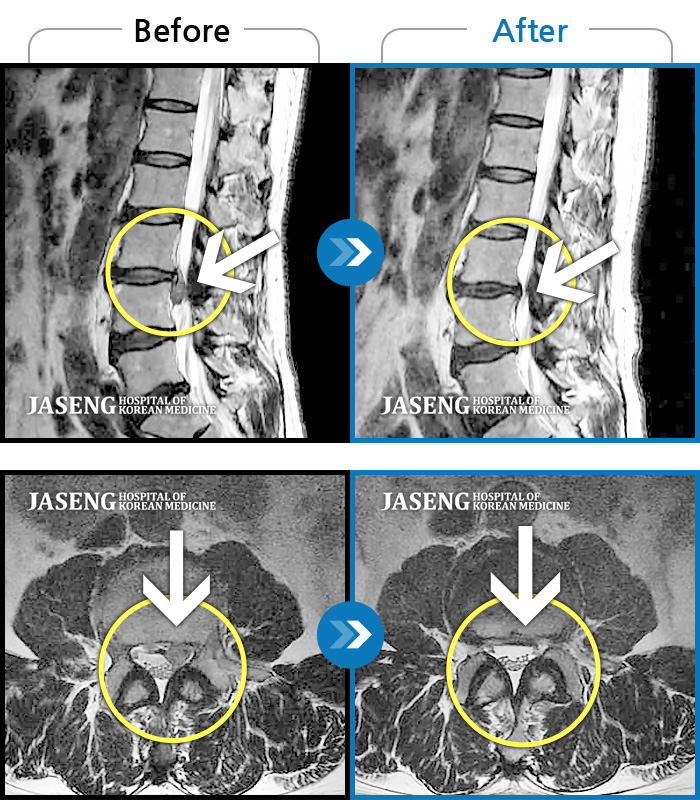

허리디스크

잠실 · 한상욱 원장

허리, 우측 엉치와 다리 후면 및 발끝까지 저림과 통증이 심하고 힘까지 빠진다.

촬영시기

2022.06.15 ~ 2022.11.11

2022.12.02